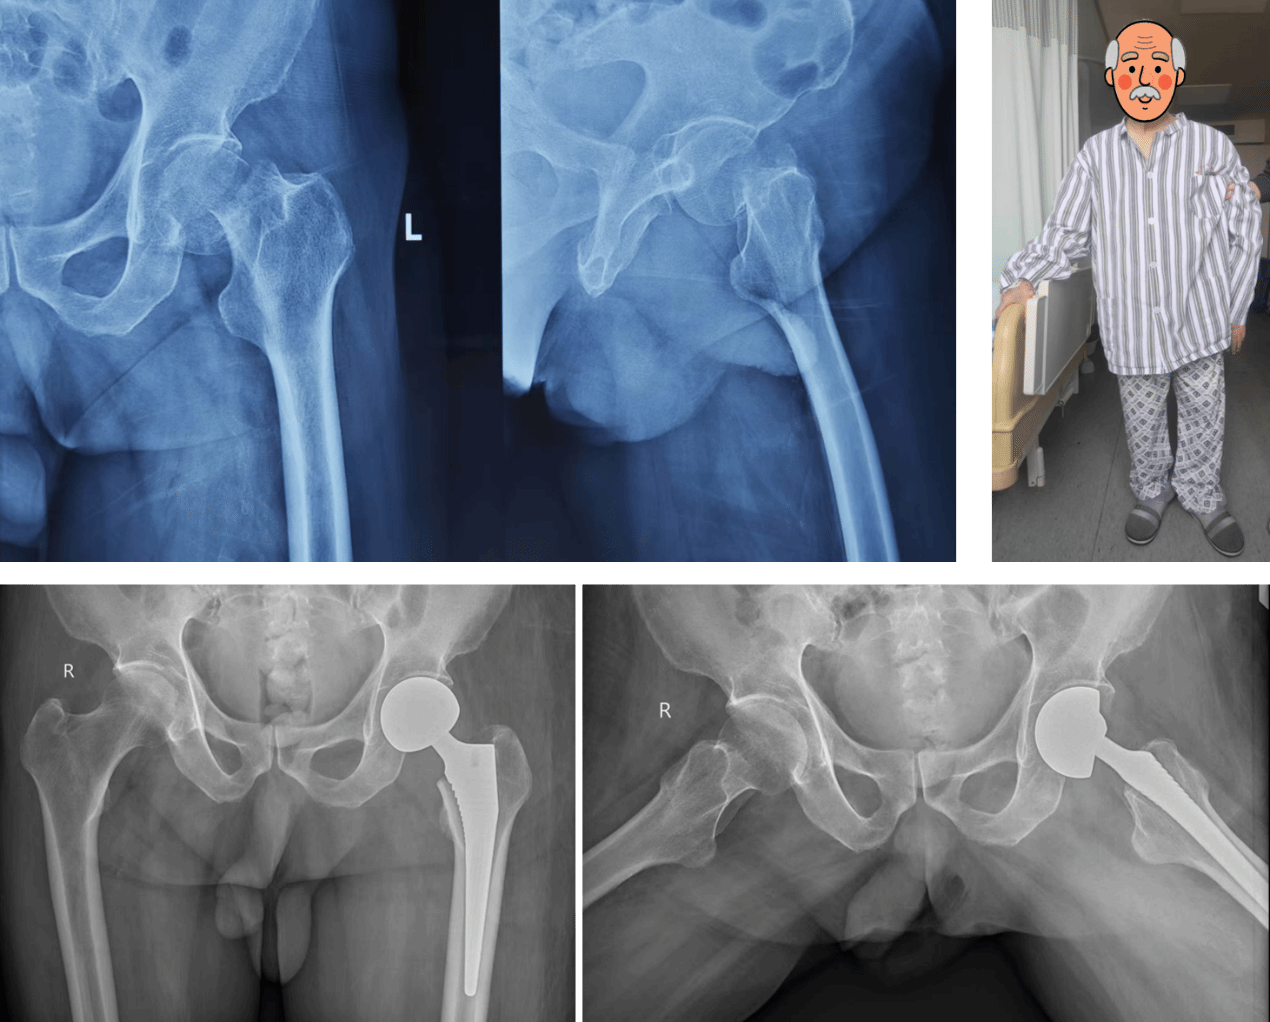

春节是一个万家团圆的日子,但90岁高龄的虞老却不慎在家中摔倒,左髋部疼痛无法活动,至当地医院就诊,诊断为左侧股骨颈骨折,按理应该立即住院手术治疗,但因为年龄过大,且有房颤等内科病史,正值春节假期,当地医院人手紧缺,不敢冒险治疗,需等到假期结束方可会诊治疗,安排手术,但1周的等待对虞老来说是非常漫长的,且可能会因为长期卧床而让虞老出现压疮、肺炎、下肢静脉血栓等并发症,故家人多方打听,慕名来到交大二附院运动医学科,在时志斌主任的主导下,院老年心血管内科、重症医学科、影像科、检验科、超声医学科、输血科、麻醉手术科等多科室密切协作,在入院48小时内便为老人安排了手术,也就是大年初六,由时志斌主任主刀,倪建龙副主任医师和吕雷锋住院总医师配合,经过40分钟的手术,虞老顺利闯关“人生的最后一次骨折”,目前虞老恢复良好,已开始下地活动,脸上也见到了久违的笑容。